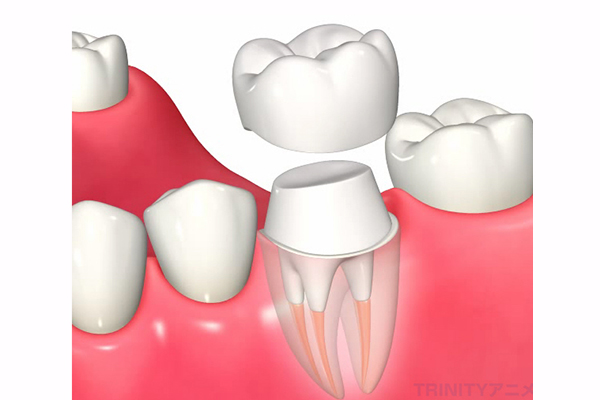

根管充填

根管内部がキレイになり、目立った症状が消失したら、根管の内部を生体親和性のある材料をつめて再感染を防止します。

その際に推奨される材料はMTAセメントですが、これは保険適応外の材料となります。

根管治療が終了したら、噛み合わせや見た目の回復ためにコア(土台)+かぶせ物の治療が必要になり、ここまで行って治療が完了します。

根管治療を成功に導くためには、正確な診断を行い、よく見える状態で感染物を除去し、適切な材料で根管を詰めることが重要です。そして、根管治療が終了後のかぶせ物(クラウン)は再発を防ぐためにはとても重要です。